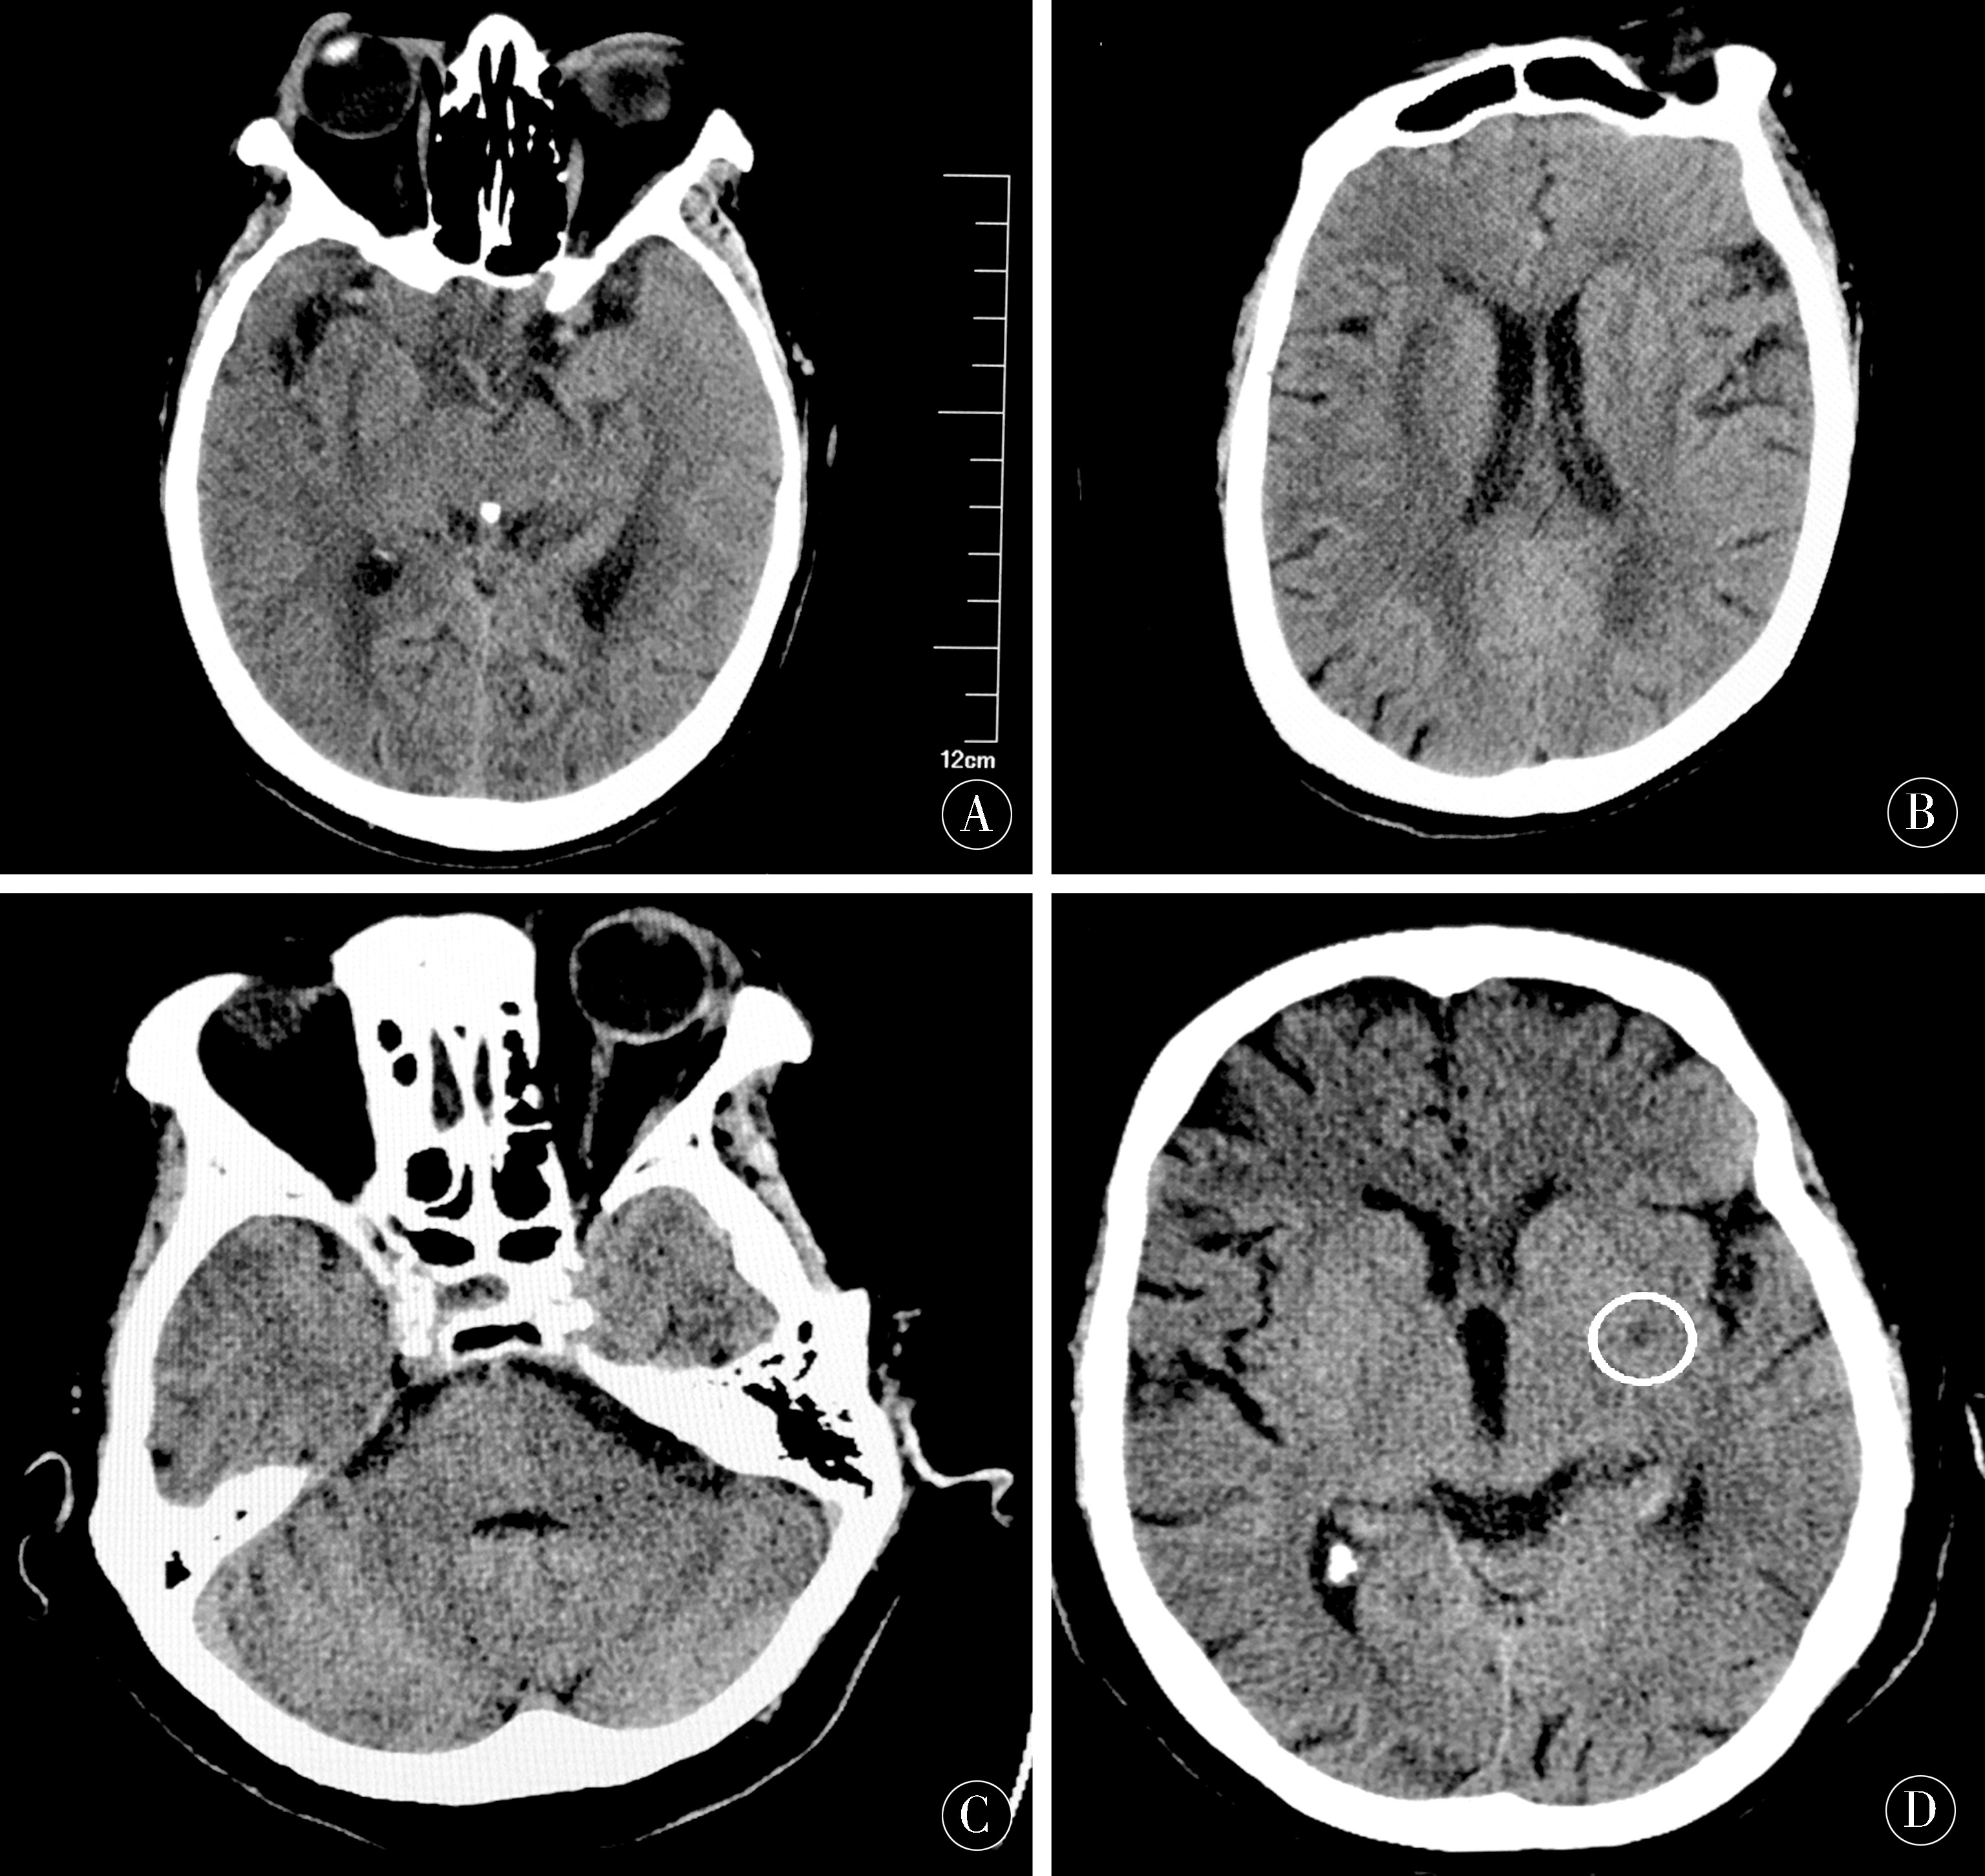

1.3.1  影像学检查:145例患者均行头部CT检查,正常126例(86.9%),异常19例(13.1%),主要表现为单侧基底节区腔隙性梗死6例,双侧基底节区腔隙性脑梗死4例,脑梗死6例,桥脑低密度灶2例。136例患者行MR或CTA检查,正常65例(47.8%),异常71例(52.2%),主要表现为腔隙性梗死27例,陈旧性梗死或缺血灶14例,脑白质脱髓鞘改变12例,脑萎缩6例,脑动脉硬化23例,颅内血管局部轻度狭窄16例,动脉瘤2例,垂体或额叶囊肿2例。CT或MR检查小脑部位均未见明显异常信号(图1~3)。

图1  A、B为患者1脑CT未见异常;C、D为患者2左侧基底节区梗死灶